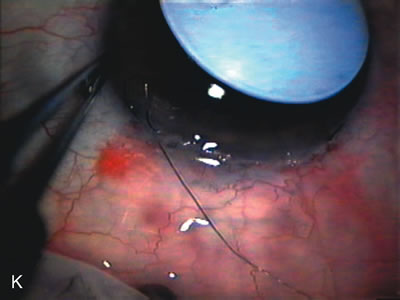

CASE 6: ANTICIPATED LENS EXTRACTION POST FAILED TRABECULECTOMY WITH ADVANCED DISC DAMAGE AND IOP OUTSIDE TARGET PRESSURE RANGE

The inflammation associated with lens extraction at any site usually causes complete failure of a marginal functioning bleb. In addition, pressure reduction by medical means is usually minimal in these recalcitrant cases, and combined surgery is indicated. In the past, these cases were approached with large-incision ECCE, clear corneal cataract incision, and bleb revision. Drawbacks included those mentioned earlier for large incision clear corneal cataract extraction, and bleb revision is often associated with conjunctival buttonholes, wound leaks, subconjunctival hematoma, destruction of friable sclera, and associated hypotony. With the advent of modern-day cataract surgery, a phacotrabeculectomy is often possible adjacent to the failed filter (Fig. 7). The ability to combine cataract extraction with implant and filtration surgery all through the same small incision has greatly improved outcomes for patients with marginal preoperative filters. There are several other viable options in this case. If the surgeon elects to remove the cataract through a temporal clear corneal incision, the bleb may be revised or a new adjacent filter fashioned. As mentioned earlier, revising a failed filter is technically challenging. If the surgeon believes it is not feasible to revise the filter or fashion a new one, a glaucoma drainage implant is a reasonable option combined with temporal lens extraction.172

Fig. 7. Phacotrabeculectomy adjacent to a failed filter in cataractous eye. The ability to combine small-incision cataract extraction with trabeculectomy all through the same incision adjacent to the failed filter allows the surgeon to work in a familiar superior area. Avoiding incisions into the existing bleb decreases conjunctival buttonholes, hypotony, operating room time, and subconjunctival bleeding. A. Appearance of failed bleb with exposure of superior temporal quadrant gained with a corneal traction suture. B. Prepare a limbus-based conjunctival flap and a scleral flap. C. This bleb is at high risk to fail again justifying the need for MMC, 0.2 mg/cc applied on a pledget for 4 minutes. D. Insert the keratome and perform phacotrabeculectomy in the usual fashion.